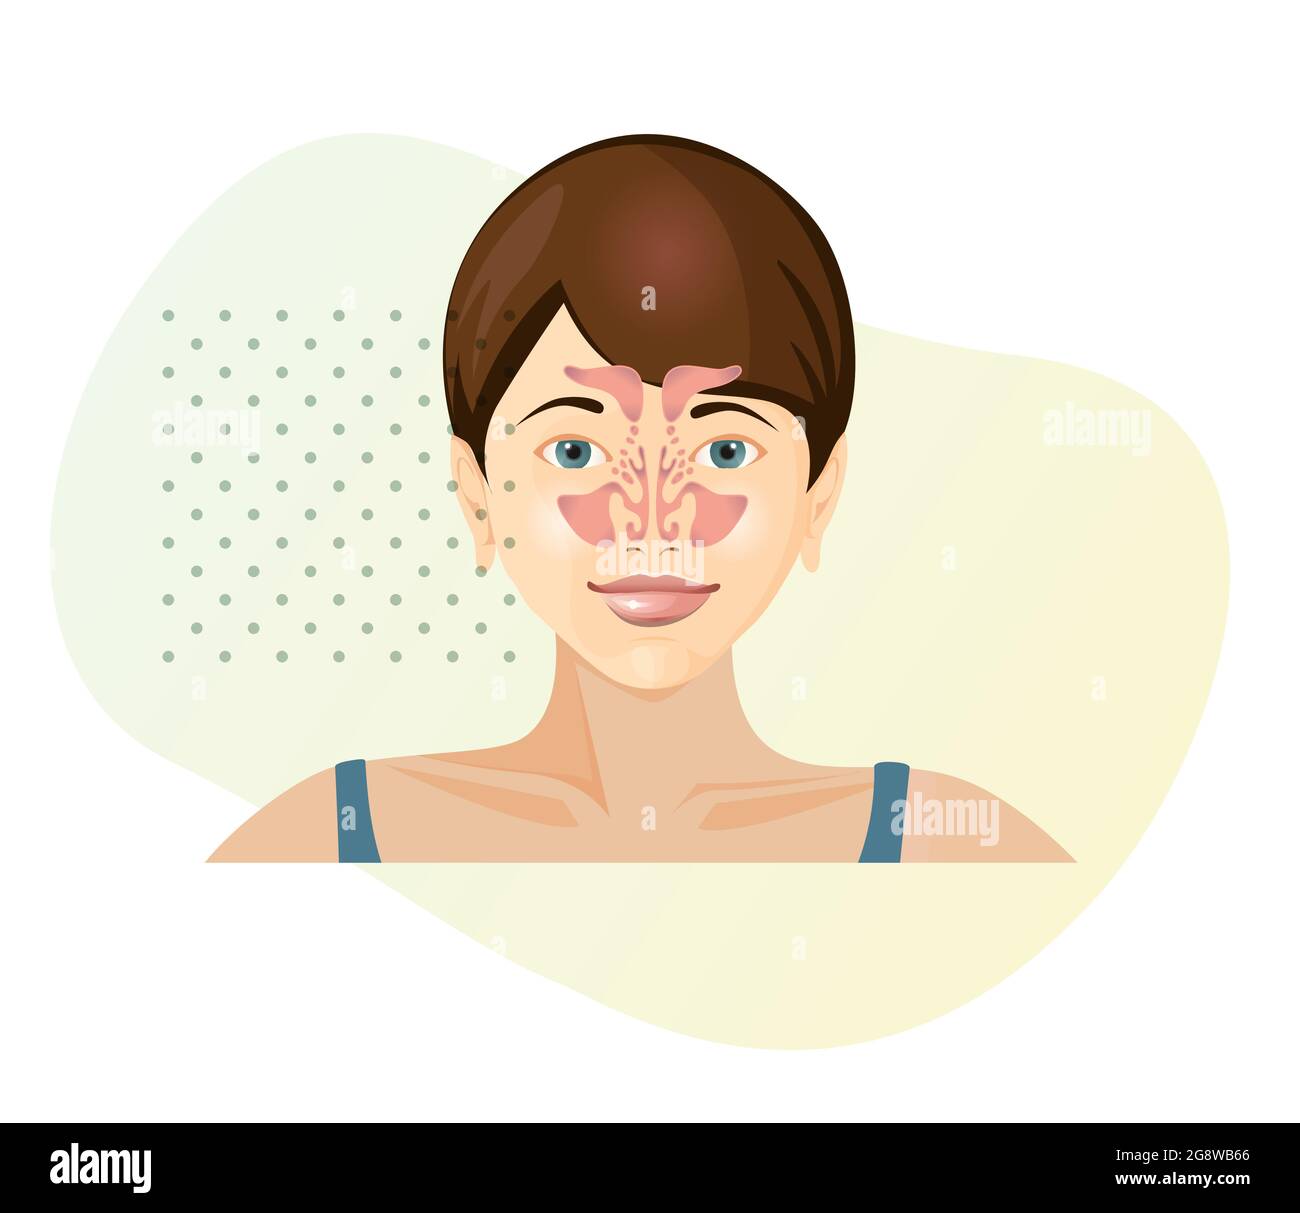

RF2MXM134–Schéma anatomique du nez et de l'oreille avec apparence et coupe transversale des organes Illustration vectorielle réaliste

RF2F9X5W7–Icône d'analyse du nez. Outline Nose Analysis vector icon for web design isolé sur fond blanc

RF2PHF7GE–Icône d'analyse du nez. Outline Nose Analysis vector icon for web design isolé sur fond blanc couleur plate